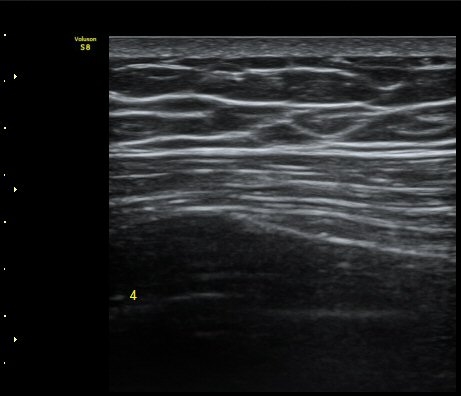

Á¾´Ü¸é°Ë»ç¿¡¼­ °¡°ñ Çü¼ºÀÌ °üÂûµÊ(formation of callus)   »çÁø 3

°¥ºñ»À Ⱦ´Ü¸é°Ë»ç¿¡¼­ °¡°ñ Çü¼ºÀÌ °üÂûµÊ(formation of callus)  »çÁø 4